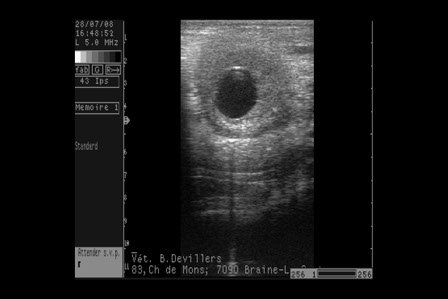

La pratique de la gynéco " à l'ancienne" n'est bien sûr pas insensée, puisqu'elle a longtemps eu lieu avant les progrès scientifiques, mais elle a ses limites, et surtout elle plonge les éleveurs dans un contexte d'inégalité criante face à la possibilité de disposer d'un souffleur et d'avoir accès aisemént à un étalon proche et disponible.

Pour faire bref, les petits éleveurs seraient violemment les victimes. Il faut également noter les cas de jumeaux qui, non détectés, mettent en péril la vie de nombreuses juments. Plus généralement, la France de l'élevage en patirait gravement dans la mesure où l'élevage se poursuit normalement Outre-Manche, avec des "fuites" de juments observées sur les routes normandes tout dernièrement. A noter qu'en Italie, selon les informations livrées encore ce soir par les Dr Vigliani et Dr Romano, contactés directement par l'italien Niccolo Riva, spécialistes équins du trot et du galop, la gynéco se poursuit suite à une décision prise par le Ministère de l'Agriculture dans les 48 heures après le déclenchement de l'épidémie, afin de protéger la filière.